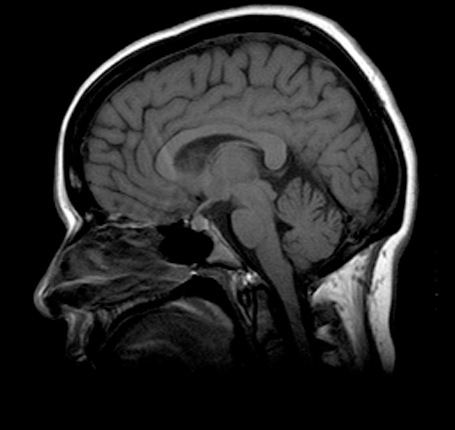

Head and Neck (Sagittal)

Cerebellum

Cerebral Hemisphere

Diencephalon

Medulla Oblongata

Midbrain

Pons

Straight Sinus

Superior Sagittal Sinus